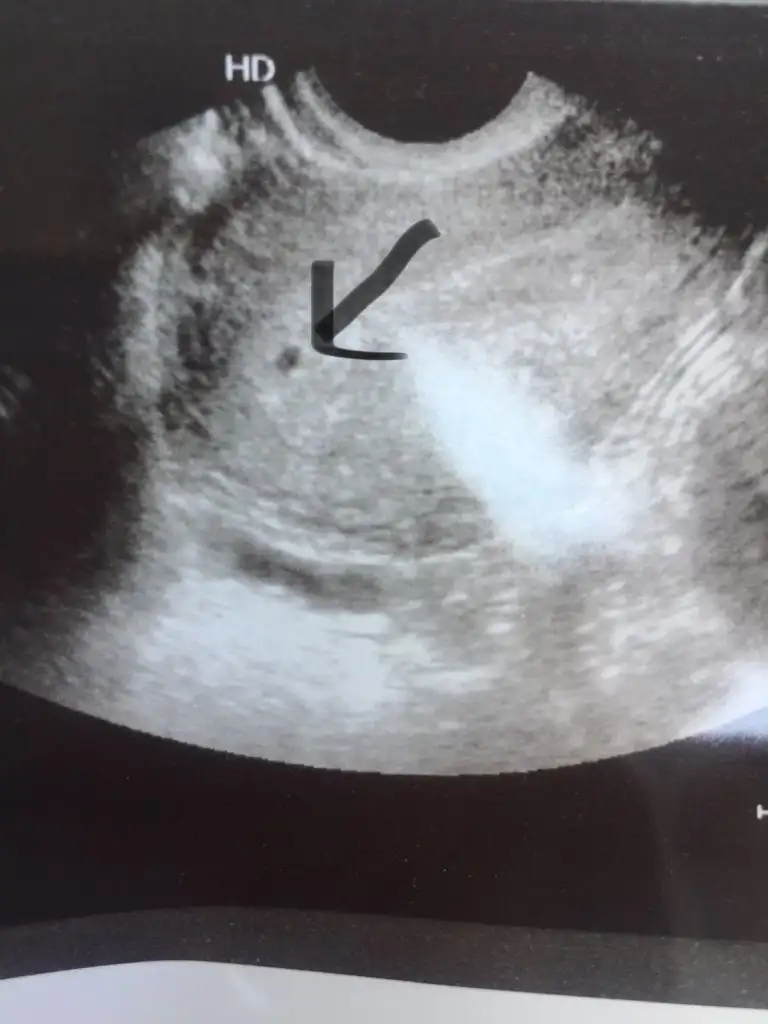

Canım bunu keseye benzetti doktor %90 normal gebelik olduğunu düşünüyorum dedi ama kesin %100 de demiyorum kan sonucuna da bakalım dedi Diğer tarafta kist çıktı ama dün kü doktor kistin falan yok demişti. Bu şimdi kesin kese değil mi dedim yalancı kese de olmuş olabilir keseye benzer birşey dedi ama kesin konuşamam dedi birde dış gebelik varsa nerdeyse görünürmüş o görünüyor mu bir yerde dedim onu hemen görmek zor dedi sonuçta bu görünen şey de kese midir ya yolk sacı falan da görmek lazım dedi anlamıyorum hiçbirşey ilk kez yaşıyorum bunuHaber ver canım

Benimde kesem o kadar küçüktü bu görüntü rahimde ise nasıl dış olabilir ki. Bence doktorunu değiştirCanım bunu keseye benzetti doktor %90 normal gebelik olduğunu düşünüyorum dedi ama kesin %100 de demiyorum kan sonucuna da bakalım dedi Diğer tarafta kist çıktı ama dün kü doktor kistin falan yok demişti. Bu şimdi kesin kese değil mi dedim yalancı kese de olmuş olabilir keseye benzer birşey dedi ama kesin konuşamam dedi birde dış gebelik varsa nerdeyse görünürmüş o görünüyor mu bir yerde dedim onu hemen görmek zor dedi sonuçta bu görünen şey de kese midir ya yolk sacı falan da görmek lazım dedi anlamıyorum hiçbirşey ilk kez yaşıyorum bunuağrım niye var ki bu kadar

doktorlar ilk zamn kesin konusmuyor zaten benmkide böle nokta gibiydi 5.haftada gitmiştim yolk sac dediği sey su an görünmez zaten o se içinde olusan başka bi kese gibi bsy oluyor bnce sizinkide kese yani niye bu kdr kafa karıştırmıski doktor cok şüpheli biri heraldeCanım bunu keseye benzetti doktor %90 normal gebelik olduğunu düşünüyorum dedi ama kesin %100 de demiyorum kan sonucuna da bakalım dedi Diğer tarafta kist çıktı ama dün kü doktor kistin falan yok demişti. Bu şimdi kesin kese değil mi dedim yalancı kese de olmuş olabilir keseye benzer birşey dedi ama kesin konuşamam dedi birde dış gebelik varsa nerdeyse görünürmüş o görünüyor mu bir yerde dedim onu hemen görmek zor dedi sonuçta bu görünen şey de kese midir ya yolk sacı falan da görmek lazım dedi anlamıyorum hiçbirşey ilk kez yaşıyorum bunuağrım niye var ki bu kadar